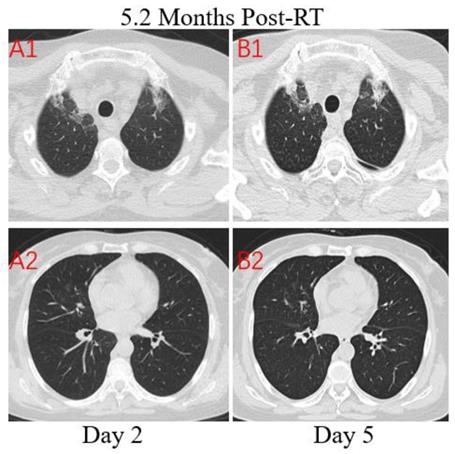

Figure 4

Transverse unenhanced thin-section serial CT scans from a 64-year-old female with suspected COVID-19 pneumonia. Chest CT images on the second day after symptom onset found minimal ground-glass opacities with partially rounded consolidation in the apexes of both lungs (A1), and multiple ill-defined patchy ground-glass opacities in the middle lobe of right lung (A2). Follow-up CT on the fifth day demonstrated no obvious change of lung lesions (B1, B2).

Patient 3: A 64-year-old woman who worked in Beijing was diagnosed with nasopharyngeal carcinoma(T3N2M0) in July 2019 and treated with definitive concurrent chemoradiotherapy followed by adjuvant chemotherapy. She presented to the hospital with a 1-day history of fever (maximum body temperature was 39.5°C), a little cough and headache on February 17, 2020. The patient traveled to Zhuhai and lived in her community where several patients were confirmed COVID-19. At admission, both lungs were clear on auscultation. Laboratory studies showed normal white blood cell, higher neutrophil, and serious lymphopenia. The concentrations of PCT, CRP, D-dimer and NT-BNP increased significantly. The T lymphocyte subsets test showed a sharp drop in CD4+ and CD8+ T cell counts. Results for influenza A and B antigen screening were negative. Chest CT images were obtained on the second day after symptom onset and indicated that there were minimal ground-glass opacities with partially rounded consolidation (Figure 4. A1) in the apexes of both lungs, conforming completely to the irradiated area of low exposure. Multiple ill-defined patchy ground-glass opacities (Figure 4. A2) were observed in the middle lobe of the right lung, considering the possibility of COVID-19 pneumonia. After 3 days of anti-viral therapy with arbidol, antibiotic treatment with sulperazone, and supportive treatment with albumin injection. Follow-up CT demonstrated no obvious changes of lung lesions (Figure 4. B1, B2). However, the patient’s symptoms improved significantly. Repeated four times of swab nucleic acid tests for the COVID-19 were negative. Finally, blood culture suggested an Escherichia coli infection. Then the patient was transferred to the Department of Oncology.